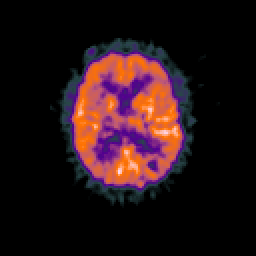

Glioma overlay -- Slice #67

[Home][Help][Clinical] Slice 67